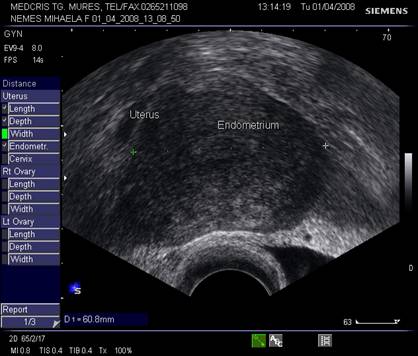

Endometrul situat in centrul uterului are contrast bine delimitat fata de corpul uterin, ecogenitatea endometrului este mai mare decat a miometrului. Vasele de la nivelul miometrului - endometrului dau o zona de contrast relativ anecogena fata de miometru - endometru.

Dimensiunile uterului la o pacienta nulipara matura, masurate transvaginal sunt de 7,3 cm x 4,0 cm x 3,2 cm. In general dimensiunile cresc cu paritatea si scad dupa menopauza.

Raportul intre corp si col este aproximativ de 1,6 in ceea ce priveste lungimea.[5,6]

Endometrul - grosimea sa este apreciata in sectiune longitudinala. Masurarea se va face de la interfata miometru - endometru la interfata identica, opusa, de pe peretele celalat uterin. Maxim acceptat normal este de 1,5 cm in perioada de premenopauza.[5] Postmenopauza in mod normal nu depaseste 5 mm, de obicei este atrofic si apare ca o imagine ecogena lineara. Daca apare o colectie anecogena postmenopauzala intrauterina, prin atrofie cervicala, aceasta colectie nu trebuie sa fie masurata la calculul grosimii endometriale.[2,6]